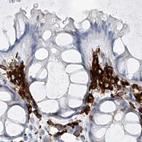

Immunohistochemistry analysis in human spleen and skin tissues using Anti-TBXAS1 antibody. Corresponding TBXAS1 RNA-seq data are presented for the same tissues.